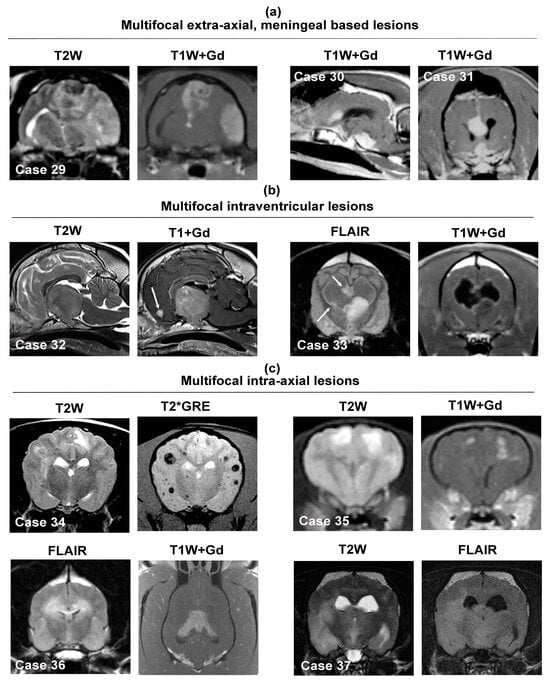

3.5. Multifocal Intracranial Neoplastic Mass Lesions

3.5.1. Multifocal Intra-Axial Mass Lesions

3.5.2. Multifocal or Diffuse Intraventricular Lesions

3.5.3. Multifocal Lesions Involving Multiple Neuroanatomic Locations